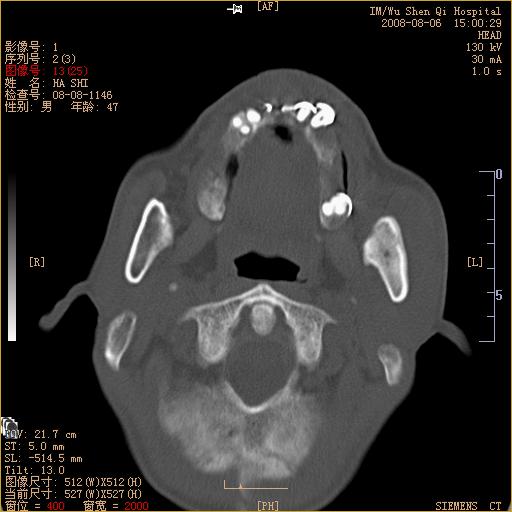

标题: CT15051:男 47岁 左下颌角部肿痛一周 [打印本页]

标题: CT15051:男 47岁 左下颌角部肿痛一周

骨质破坏,无硬化边,周围软组织肿胀,占位

左下颌骨感染性病变,牙源性可能。

左侧下颌智齿阻生。

考虑左下颌骨骨髓炎。